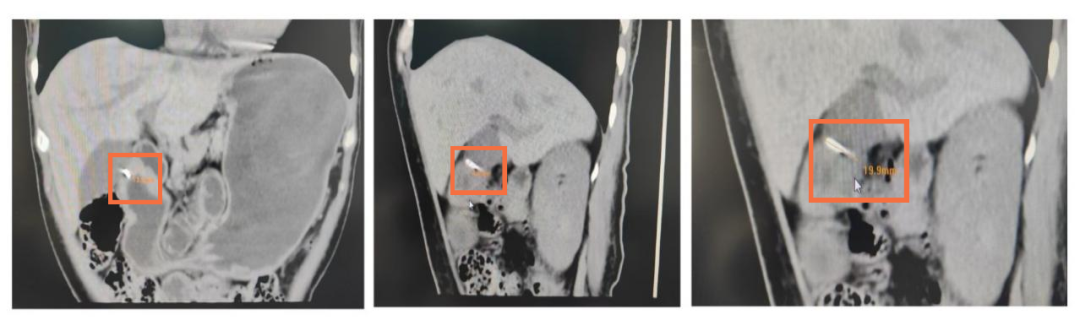

CT发现体内金属异物

这次,谜底终于露出了蛛丝马迹。影像显示,她的胃壁内可见一个细长的条状高密度影。这个影子非常隐蔽,在普通检查中很容易被忽略。结合她最初咽喉刺痛的经历,医生们判断:这很可能是一个被胃壁完全包裹的异物。就像“潜水艇”潜入了深海,它藏在胃壁肌肉里,导致多次胃镜观察胃内表面都“风平浪静”,无法发现。